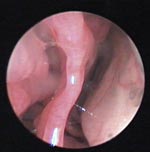

4. Blick in den Nasengang eines Schäferhundes.

5. Die Spitze der Untersuchungszange hat ein Viertel der Größe eines Streichholzkopfes. Durch das Rhinoskop sieht alles viel größer aus.